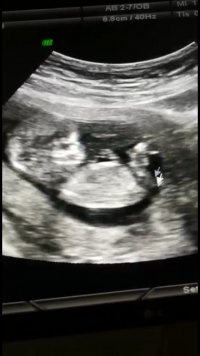

Selamlar, Ultrason sonucuna göre cinsiyet tahmini var tabiki NUB TEORİSİNE GÖRE CİNSİYET başlıklı konumuzdan resimleri nasıl atacağınız ifade edilmiştir. Hemen konuda aşağıda yer alan özellikle cinsiyet belirlemede olması gereken çıkıntıların çıktısının olması gerekiyor. Bu resimlerin büyüğü var ise gönderin bize ya da linkini verdiğimiz konuya bakarak kendiniz de tahminde bulunabilirsiniz.

Canim benimkinde bakar mısın 12+1

Ekli dosyalar

• IMG_20211118_153757.jpg

IMG_20211118_153757.jpg

2 MB · Görüntüleme: 255

• IMG_20211118_153746.jpg

IMG_20211118_153746.jpg

1,6 MB · Görüntüleme: 261

• Screenshot_20211118-152347.jpg

Screenshot_20211118-152347.jpg

627 KB · Görüntüleme: 253